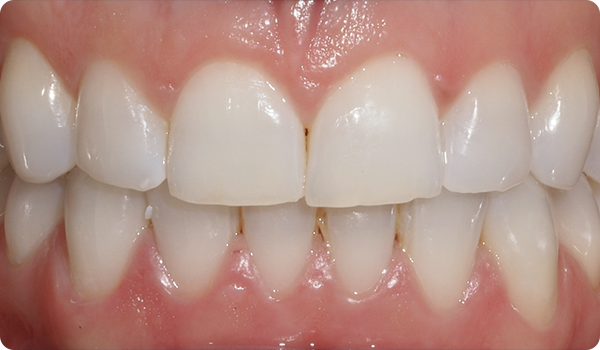

Med små rörelser korrigeras positioner och förbereder den mest lämpliga och konservativa estetiska behandlingen för dina patienter.

Leenden på plats

Med Right får dina patienter det leende de önskar, inom den tid de vill, på ett bekvämt och ”osynligt” sätt.

Att justera tänder med Right är den perfekta och mest konservativa grunden för framtida blekning eller facettbehandlingar som kommer att föra patientens leende till perfektion.